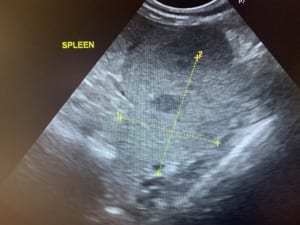

症例2:パピヨンの脾臓摘出

↑ 健康診断のエコー検査にて、脾臓に腫瘤を認めたため、飼い主様と相談の上、摘出することにしました。